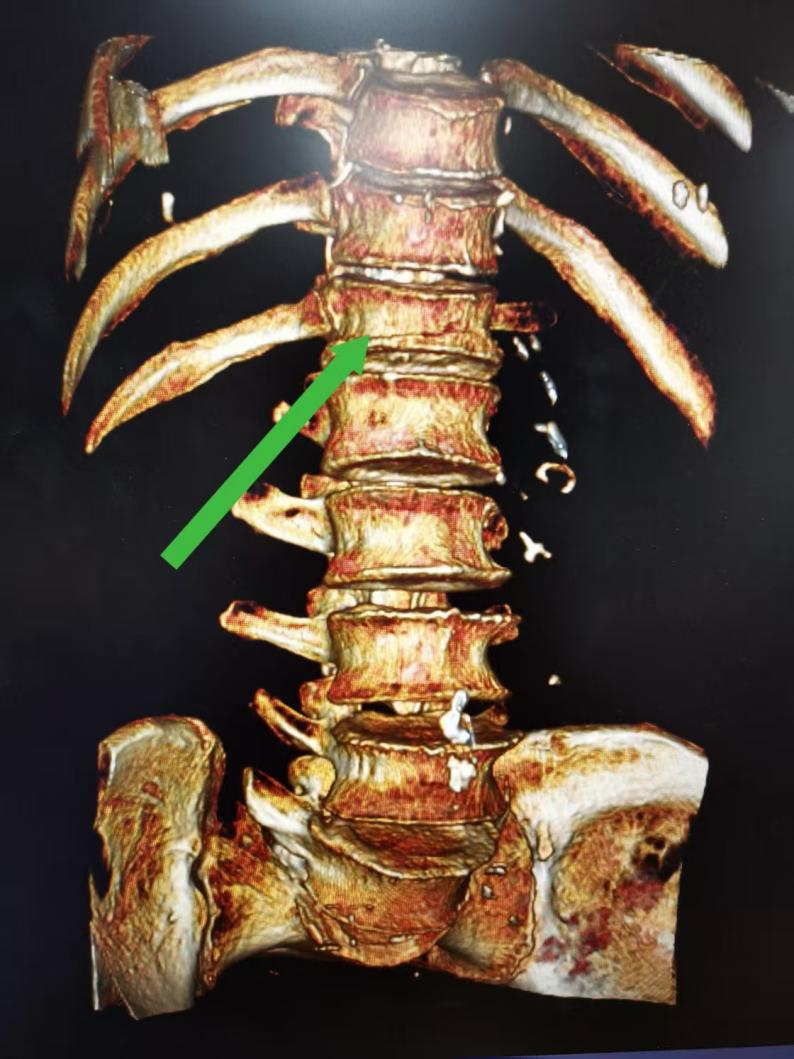

术前CT三维重建显示 第12胸椎压缩骨折(箭头所示)